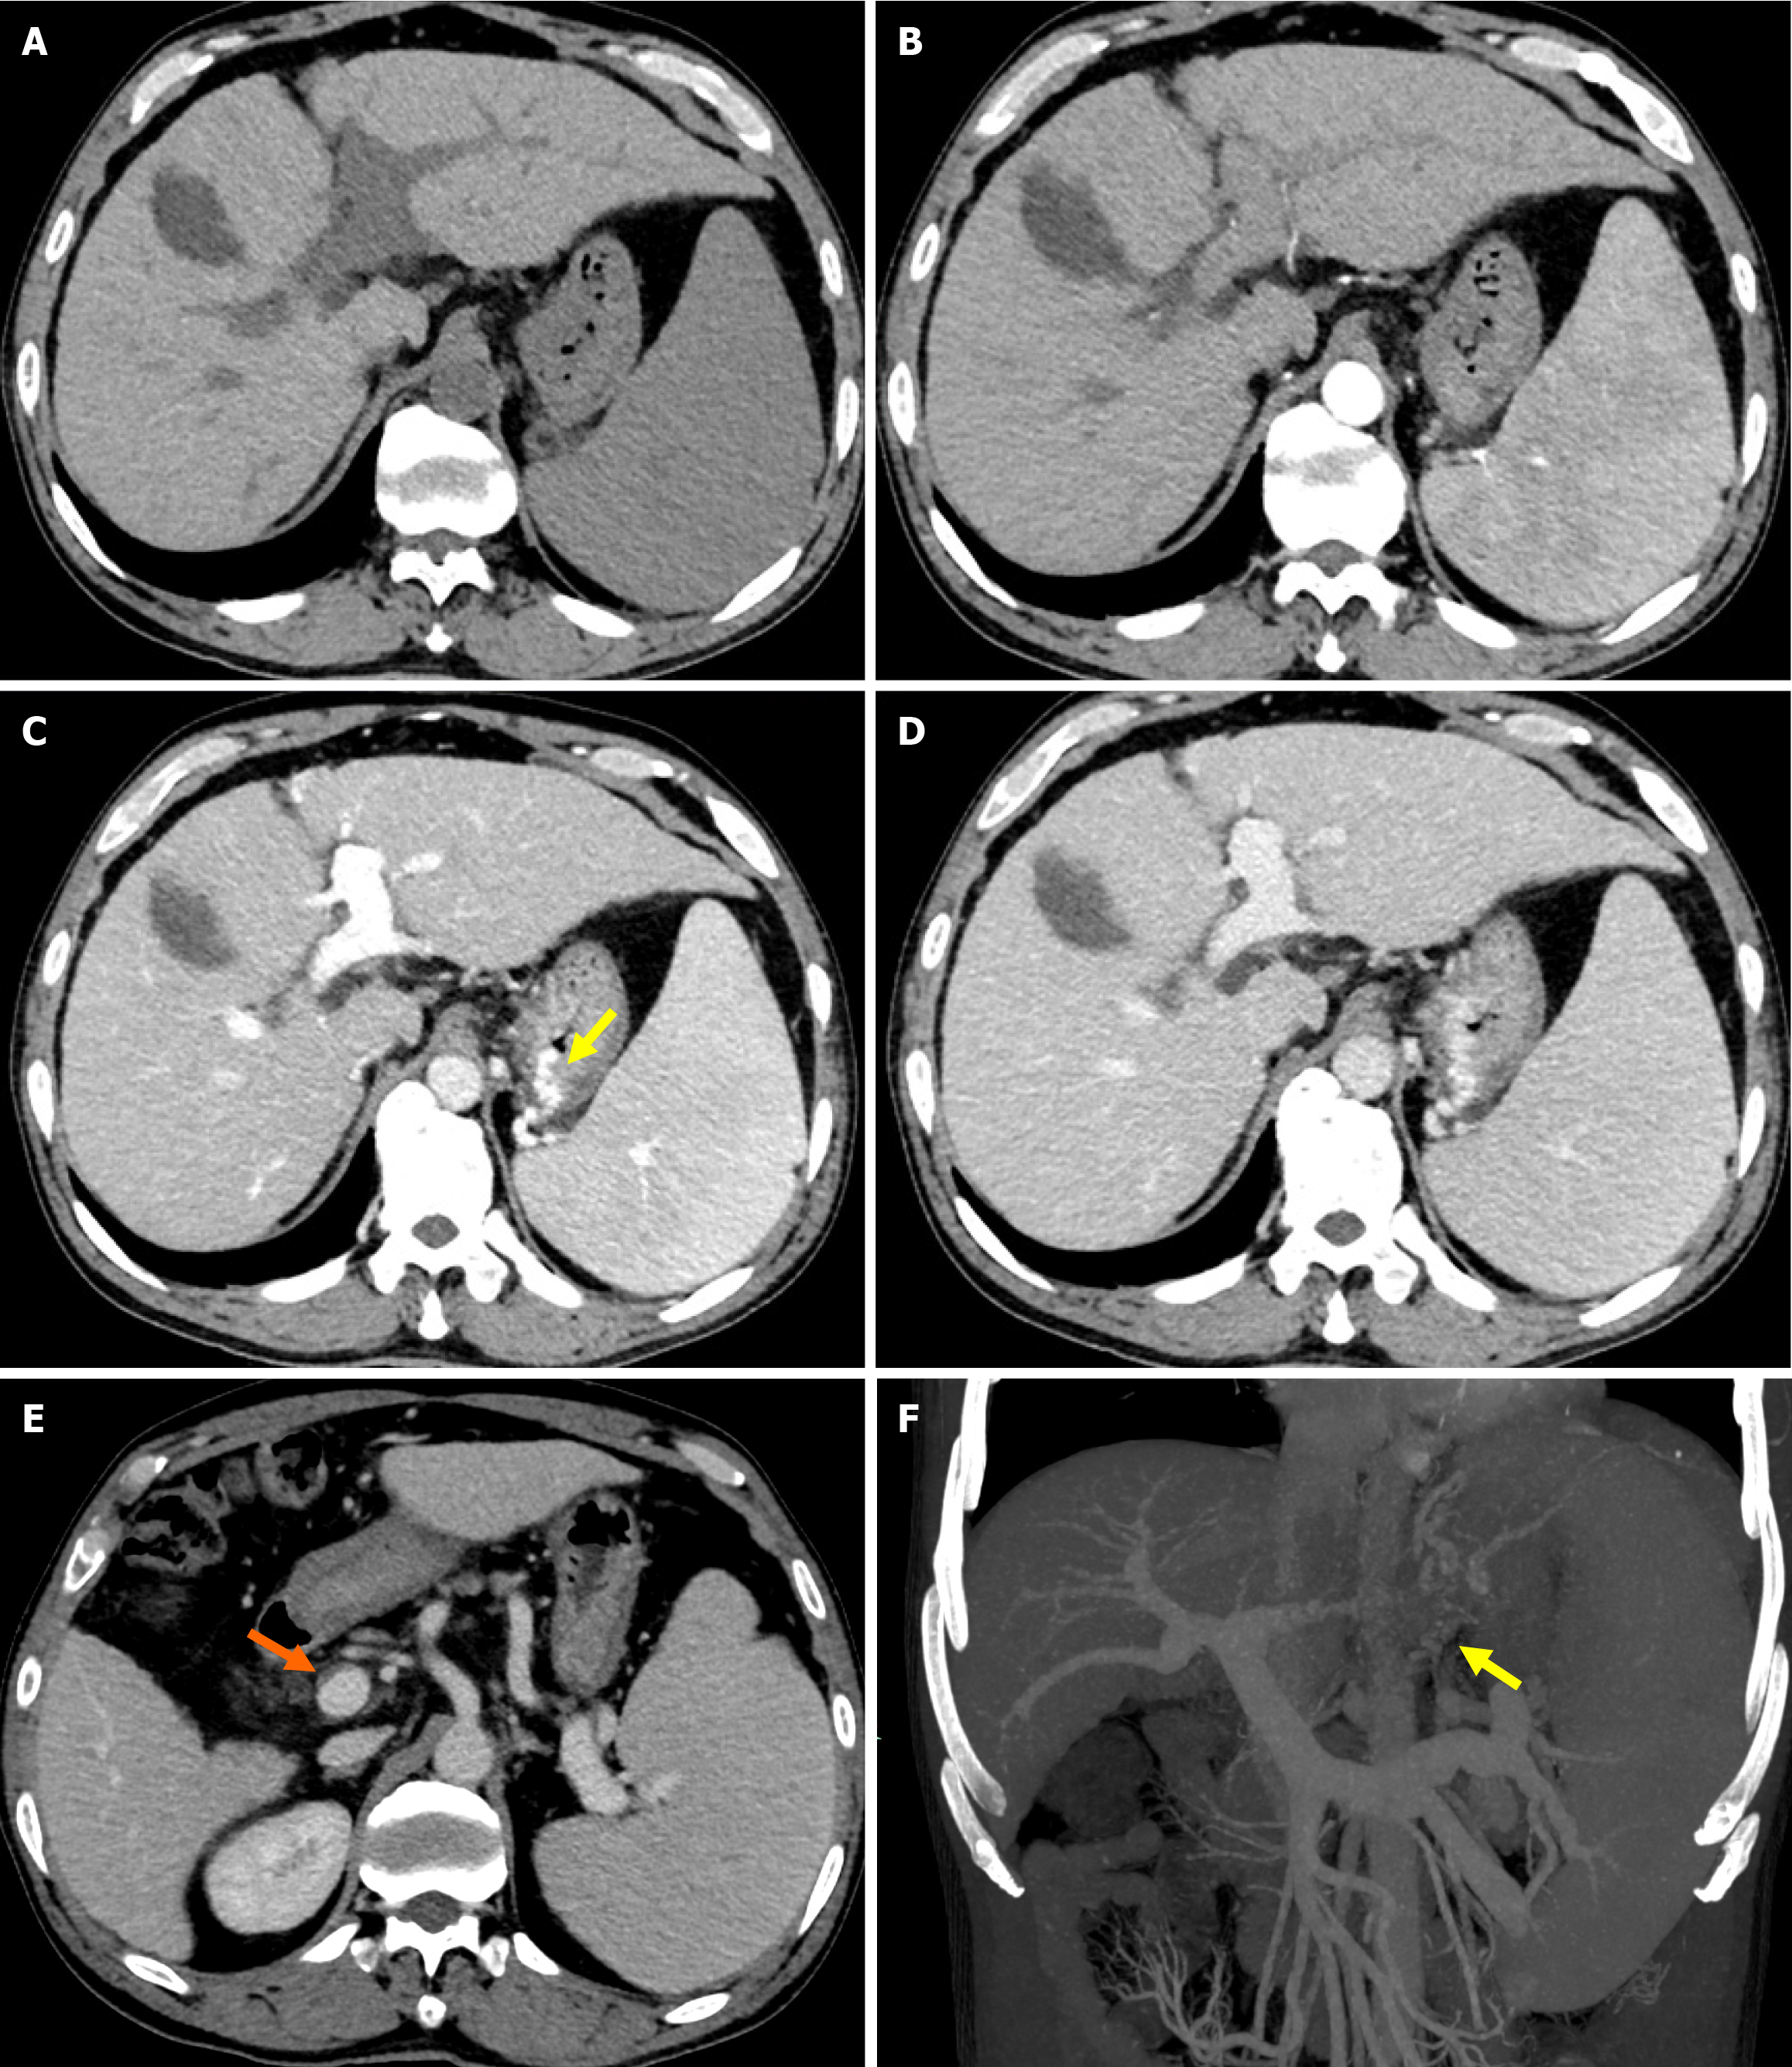

Following the procedure, melena disappeared immediately and the patient was transferred out on day 3. And the patient was advised to undergo follow-up liver CT angiography at 1 and 3 months postoperatively to assess shunt patency and monitor for the development of hepatocellular carcinoma. Subsequent evaluations should then be performed every six months thereafter. CT images one month after TIPS creation revealed metallic continuity of the stents (Figure 3B). However, follow-up CT imaging at 15 months post-procedure demonstrated stent fracture at the hepatocaval confluence (Figure 3C), although notably, the stent lumen remained patent (Figure 3D). A 20 mm stent fragment was radiologically confirmed to be lodged within the infra-diaphragmatic segment of the IVC, exhibiting positional stability without evidence of proximal migration toward the right atrium on serial imaging surveillance. The patient was treated conservatively as he was asymptomatic. CT images and color Doppler ultrasound 14 months after the procedure demonstrated neither further stent fracture nor further dislocation of the stent fragment. No symptoms associated with the stent fracture were observed for 15 months. However, the patient was readmitted 30 months post-TIPS due to recurrent esophagogastric variceal bleeding and ascites. Enhanced abdominal CT indicated occlusion of the original shunt (Figure 4). An attempt to revise the dysfunctional shunt via a stent-in-stent approach was conducted but was unsuccessful. Con

There is no consensus on the management of stent fractures. Treatment mainly depends on the type of stent fracture, clinical symptoms and potential risks[3,13]. Stent fracture can be classified as type I (no loss of stent integrity), type II (loss of stent integrity), and type III (separation or embolization of the fractured segment)[15]. Treatment of type I and type II stent fractures is typically performed using interventional procedures to insert a second stent to stabilize the fractured parts (stent-in-stent maneuver)[16]. However, surgery may be required to retrieve the distally migrated fragment in type III stent fractures, as the fragment can move into the right atrium, right ventricle and the pulmonary artery resulting in conduction abnormalities, valvular damage, perforation and possible death[17]. Fortunately, this rarely occurs. Komaki et al[13] reported a patient with a type III stent fracture after TIPS who was treated conservatively as he was asymptomatic for 15 months and follow-up CT images demonstrated neither further stent fracture nor further dislocation of the stent fragment. Two similar cases with type III stent fractures caused no acute mechanical complications and were managed conservatively[3,12]. In our case, the patient developed a type III stent fracture but the fragment did not migrate distally. He was treated conservatively as he was asymptomatic. Unfortunately, the patient was hospitalized due to recurrent esophagogastric variceal bleeding and ascites caused by shunt thrombosis 30 months later. Following failed attempts to recanalize the original shunt, a successful parallel TIPS was established via the proximal end of the fractured stent to decompress the portal venous system, effectively mitigating the variceal bleeding and ascites. Additionally, the anchoring effect of the newly implanted stent minimized the risk of stent fragment migration into the right atrium, right ventricle, and pulmonary artery. After parallel TIPS, the patient experienced no further episodes of bleeding or ascites, and is currently under follow-up observation.